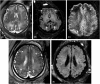

Human cytomegalovirus (CMV) is an ubiquitous pathogen, with a high worldwide seroprevalence. When acquired in the prenatal period, congenital CMV (cCMV) is a major cause of neurodevelopmental sequelae and hearing loss. cCMV remains an underdiagnosed condition, with no systematic screening implemented in pregnancy or in the postnatal period. Therefore, imaging takes a prominent role in prenatal diagnosis of cCMV. With the prospect of new viable therapies, accurate and timely diagnosis becomes paramount, as well as identification of fetuses at risk for neurodevelopmental sequelae. Fetal magnetic resonance imaging (MRI) provides a complementary method to ultrasound (US) in fetal brain and body imaging. Anterior temporal lobe lesions are the most specific finding, and MRI is superior to US in their detection. Other findings such as ventriculomegaly, cortical malformations and calcifications, as well as hepatosplenomegaly, liver signal changes and abnormal effusions are unspecific. However, when seen in combination these should raise the suspicion of fetal infection, highlighting the need for a full fetal assessment. Still, some fetuses deemed normal on prenatal imaging are symptomatic at birth or develop delayed cCMV-associated symptoms, leaving room for improvement of diagnostic tools. Advanced MR sequences may help in this field and in determining prognosis, but further studies are needed.